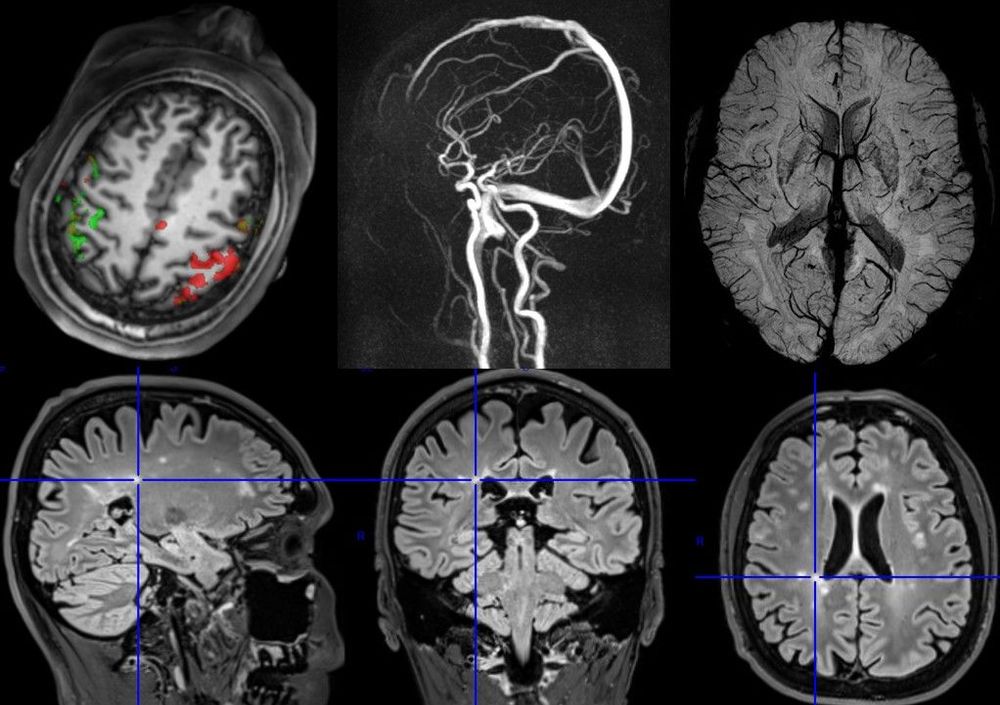

Rozsáhlý soubor přednášek o principech i aplikacích magnetické rezonance naleznete v následujícím souboru.

Tento „Prostor MR“ je výsledkem dlouholeté práce a měl by sloužit k edukaci radiologických asistentů, lékařů, fyziků a dalších odborníků v oblasti magnetické rezonance